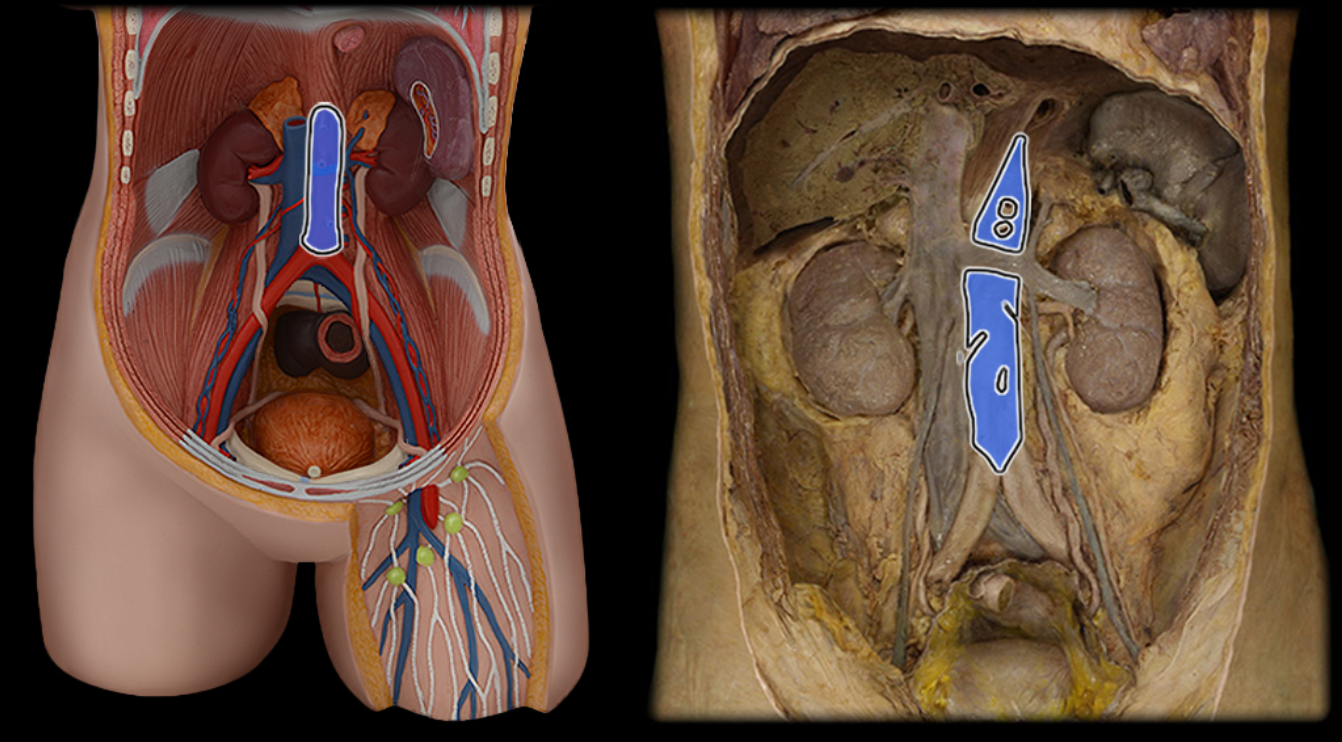

Abdominal aorta

Celiac a.

Common iliac a.

Common iliac v.

External iliac a.

External iliac v.

Femoral a.

Femoral v.

Gonadal a.

Gonadal v.

Great saphenous v.

Inferior mesenteric a.

Inferior vena cava

Lumbar a.

Lumbar v.

Renal a.

Renal v.

Superior mesenteric a.